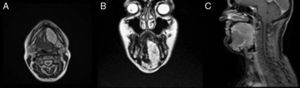

Tras la ausencia de un diagnóstico claro de la tumoración, se decidió realizar una RM, en la que se observó la existencia de una tumoración de unos 6,4×5,8×3,2cm de diámetro, localizada en suelo de boca izquierdo que se extendía a zona submental, con señal isointensa en T1 y marcadamente hiperintensa en T2 (fig. 2), con calcificaciones en su interior, con el diagnóstico de presunción de tumoración vascular con flebolitos en su interior.